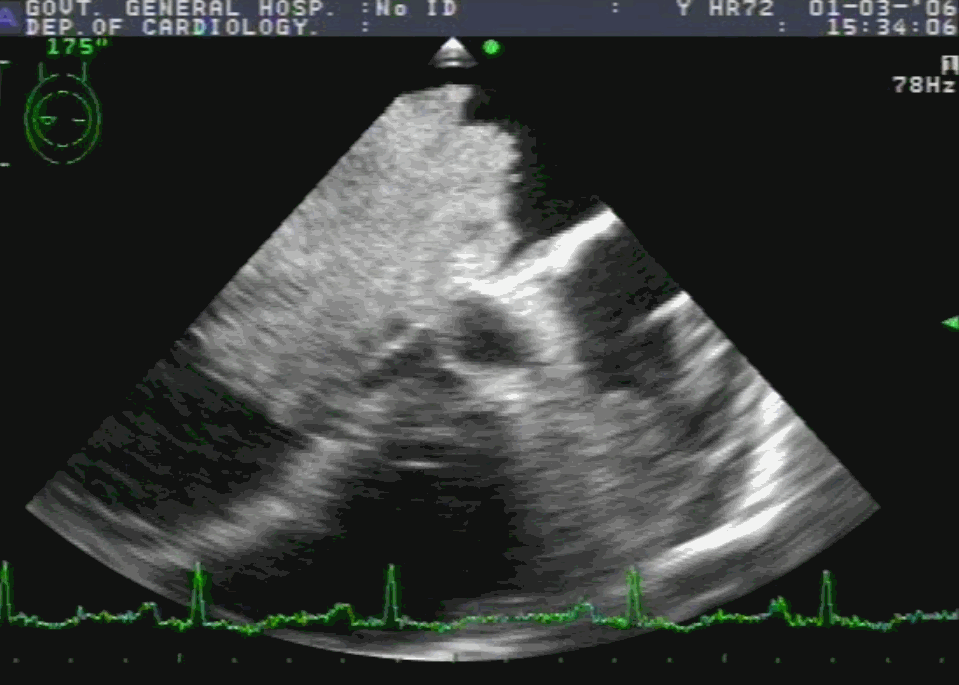

RA myxoma attached to septum: Image source -Michael Essandoh from Research gate

Cardiac myxoma is the most common primary tumor of the heart that presents as mitral inflow obstruction/ regurgitation often with a systemic presentation. It can be either familial, syndromic, or sporadic. Excellent imaging is possible and diagnosis has become straightforward. Surgery is the specific treatment,

What information do the Surgeons need?

Size, attachment to surrounding structures is the key. The myxoma origins most often in IAS and defining its attachment is crucial. Mitral leaflet distortion, Injury ( and even attachment) is possible. It is helpful for the surgeons if we let them know the mechanism of mitral regurgitation prior to surgery. Echocardiogram including TEE is sufficient in most. MRI may add some more info. The aim of surgery is to remove the tumor mass completely.

Note 50 % tumor mass enters the left ventricle with diastole. No wonder, as the tumor plops with diastolic cardiac cycle a high-pitched sound simulating opening snap followed by an MDM perfectly mimics rheumatic mitral stenosis. An MR murmur is equally common.

4 chamber view showing what appears to be a small narrow pedicle attaching to IAS. Please note echo imaging can be deceiving. Surgeons must inspect the mass in toto before taking the decision to excise IAS or not

TEE imaging of LA myxoma. Note how fragile the edges of the tumor looks. It explains the high incidence of tumor embolus in this condition. Also, to be noted is the forceful impact of the tumor mass on AML that predisposes chronic mitral valve damage.